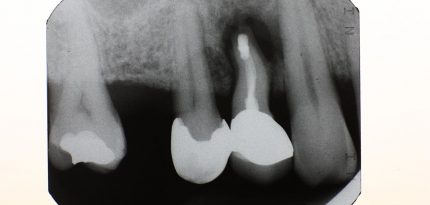

Periapical X-rays (PA)

A PA x-ray takes a full tooth picture from the very top of the tooth (crown) to the very tip of the root and its surrounding bone. This is essential for detecting infections around the roots and is an essential x-ray for detecting root canal infections.

Periapical X-ray (PA)